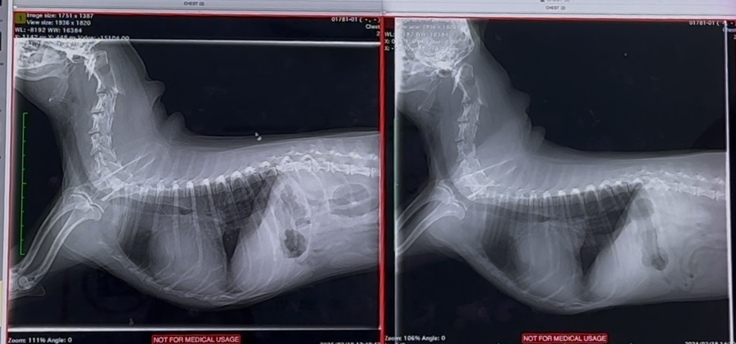

華の心臓は、術前、術後で

大きさはあまり変わっておらず

左心房の大きさは

今も、正常の倍はあり

逆流も、少し残っており…

右心の三尖弁逆流もあります

抗血栓薬を、今も飲み続けています